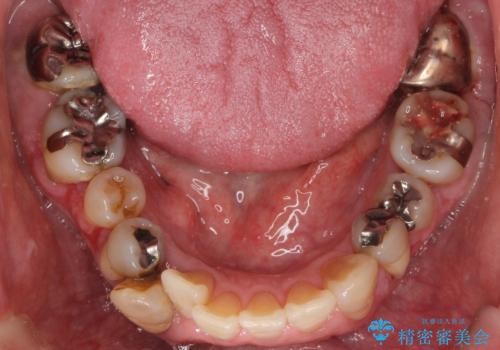

- 全顎的な重度歯周病の患者様です。

埋伏していた親知らず、保存不可能な右下の一番奥の歯(右下7)、状態の悪い犬歯(右下3)は抜歯しております。

※右上臼歯部のインプラント治療はこちらです。→https://seimitsushinbi.jp/case/67849/